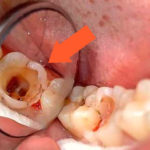

Дырка в зубе фото Дырка в зубе фото Дырка в зубе фото Глубокий кариес фото Глубокий кариес фото Глубокий кариес фото Глубокий кариес и пародонтоз Начальный кариес на зубах Глубокий кариес после родов